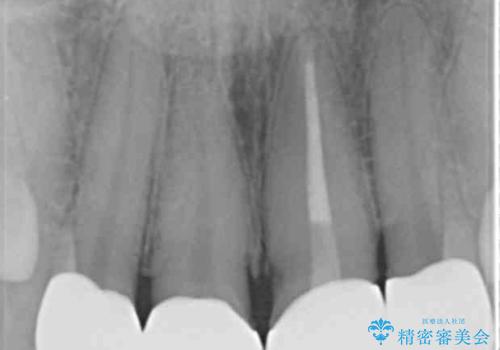

- 前歯をきれいにしたいとのご希望により来院された患者様です。

ご希望により、上の前歯4本のセラミッククラウンによる補綴治療を行いました。

- ¥572,000 (根管治療×1本、土台×1本、仮歯×4本、クラウン×4本) ※税込費用は治療当時の料金となります

クラウンの種類:オールセラミッククラウン スタンダード